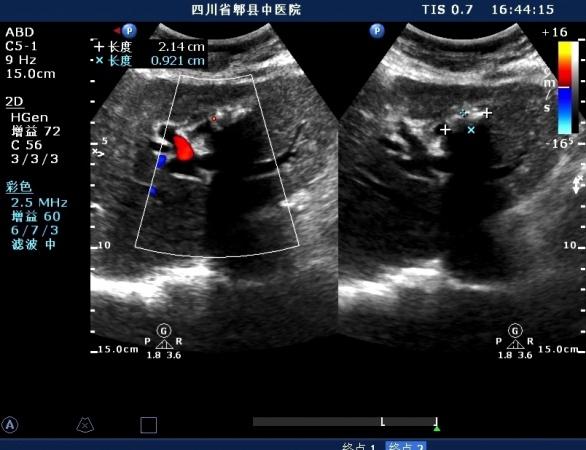

超声如图:胆总管及肝内胆管扩张,呈“平行管征”,胆总管胰腺段可见疏松强回声团堆积,后方可见淡淡声影,左肝外叶胆管内亦可见数个强回声团堆积,后方伴声影。 肝脏及胆总管

扩张的胆总管

胆总管胰腺段结石